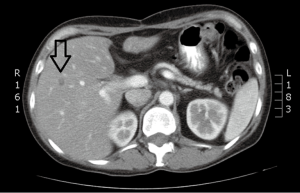

Case discussion 2 (Figure 6)

A 45-year-old woman with a diagnosis of diffuse liver metastases due to colon cancer requires a chemotherapy holiday due to neuropathy from therapy. She has been treated with FOLFOX and FOLFIRI. Given the diffuse nature of her liver metastases and clinical situation, Y90 radio-embolizaiton was recommended. Chemoembolization was considered to be an option but available results have shown better outcomes for smaller volume disease.